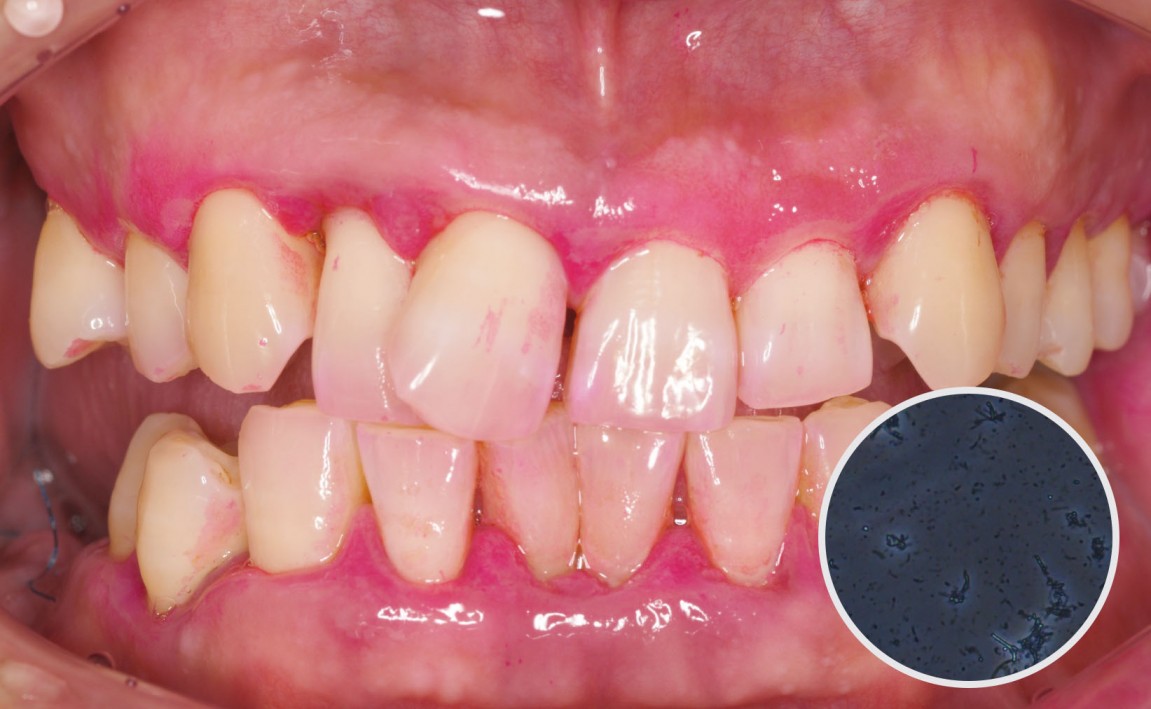

후.jpg

치료후 : 2024-08-21